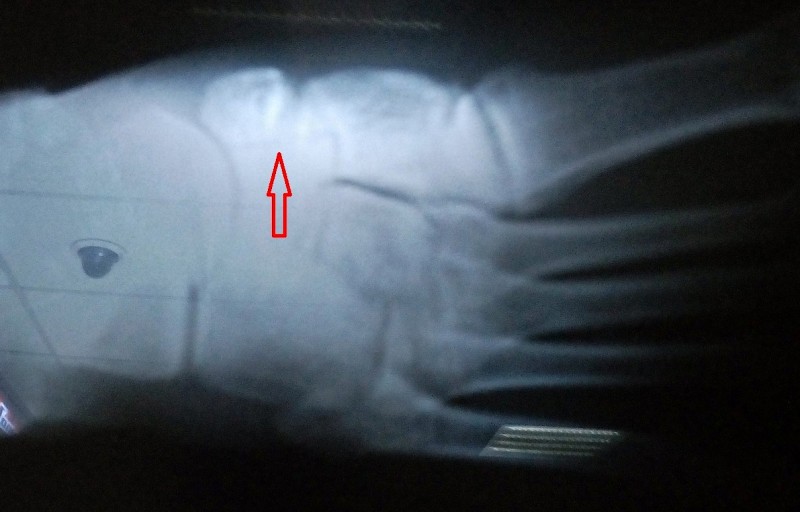

Сломано не садится

Сломано не садится 110 фото